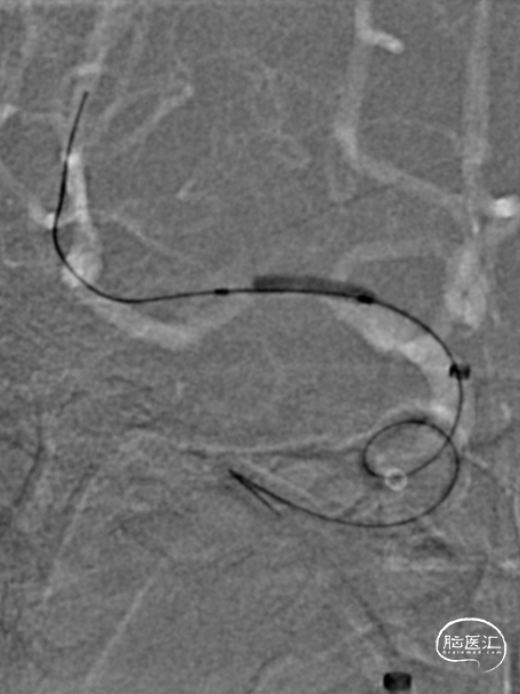

将Synchro(0.014×300cm)微导丝外衬Gateway(2.0×15mm)球囊缓慢通过RMCA M1段狭窄处,球囊定位于RMCA狭窄处缓慢扩张,压力6atm。采用交换技术置入灌注微导管,并将4.0×16mm支架定位于狭窄处释放。

复查造影见支架展开良好,支架内及远端血流通畅,TICI分级3级。术顺,术毕,Proglide缝合术口。